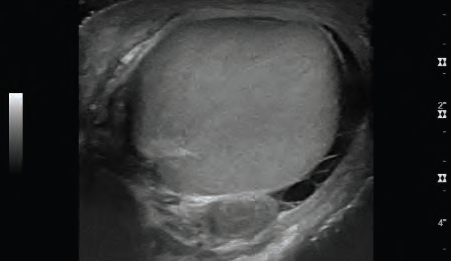

Case A 37-year-old white male with no past medical history presented to the emergency department (ED) for…